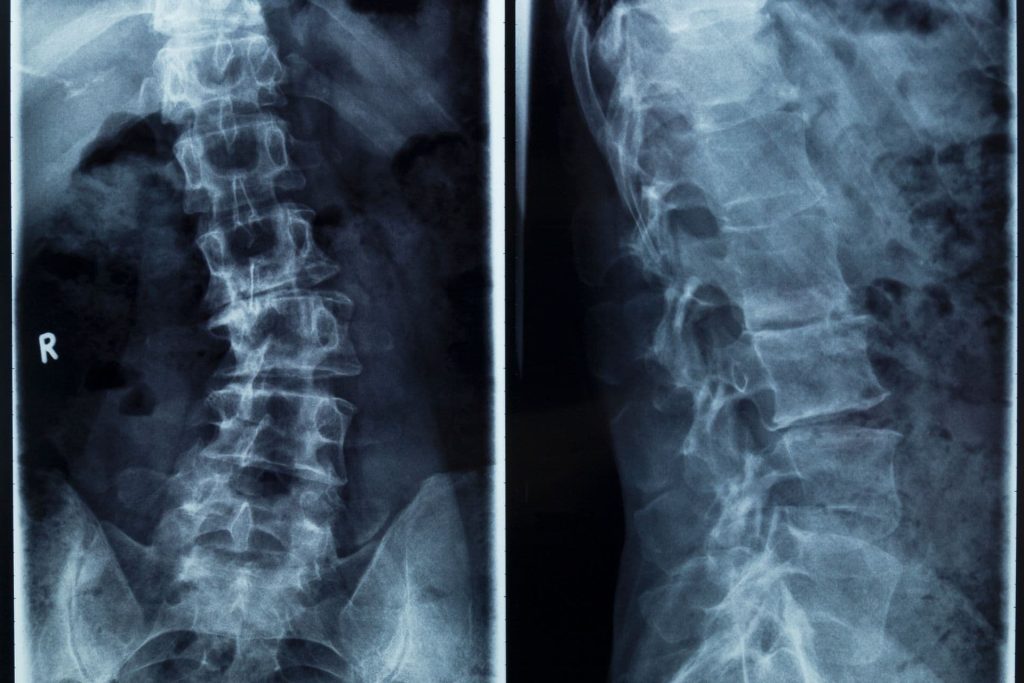

Gerincferdülés (scoliosis) tünetei és kezelési lehetőségei

Gerincferdülés (latinul: scoliosis) során a gerinc oldalirányba, azaz balra vagy jobbra görbül. A jelei már pubertáskor előtt megfigyelhetők, és a scoliosis még idejében gyógyítható. Felnőttként…